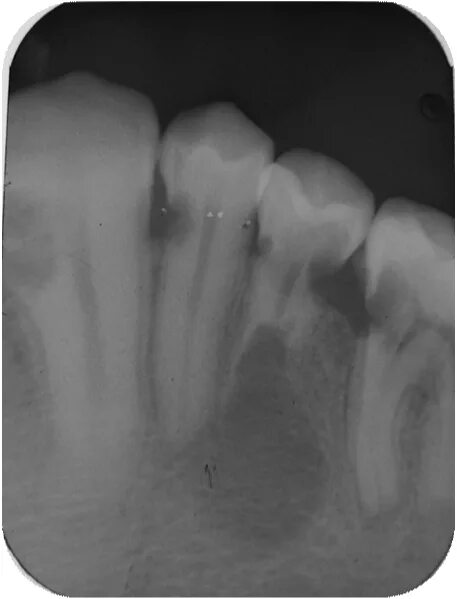

Признаки резорбции